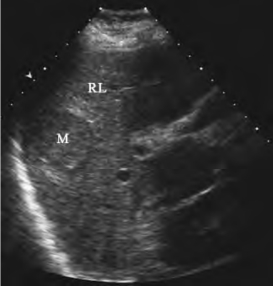

9.超声造影检查 原发性肝癌大多数在造影动脉相整体增强呈高回声,门脉相呈等回声或低回声,延迟相为低回声,表现为“快进快出”型(图23-18)。

图23-18 原发性肝癌超声造影

A图为超声造影动脉相,肿瘤整体增强呈高回声(↓)所示,B图

为延迟相呈低回声(↓)所示,表现为“快进快出”型